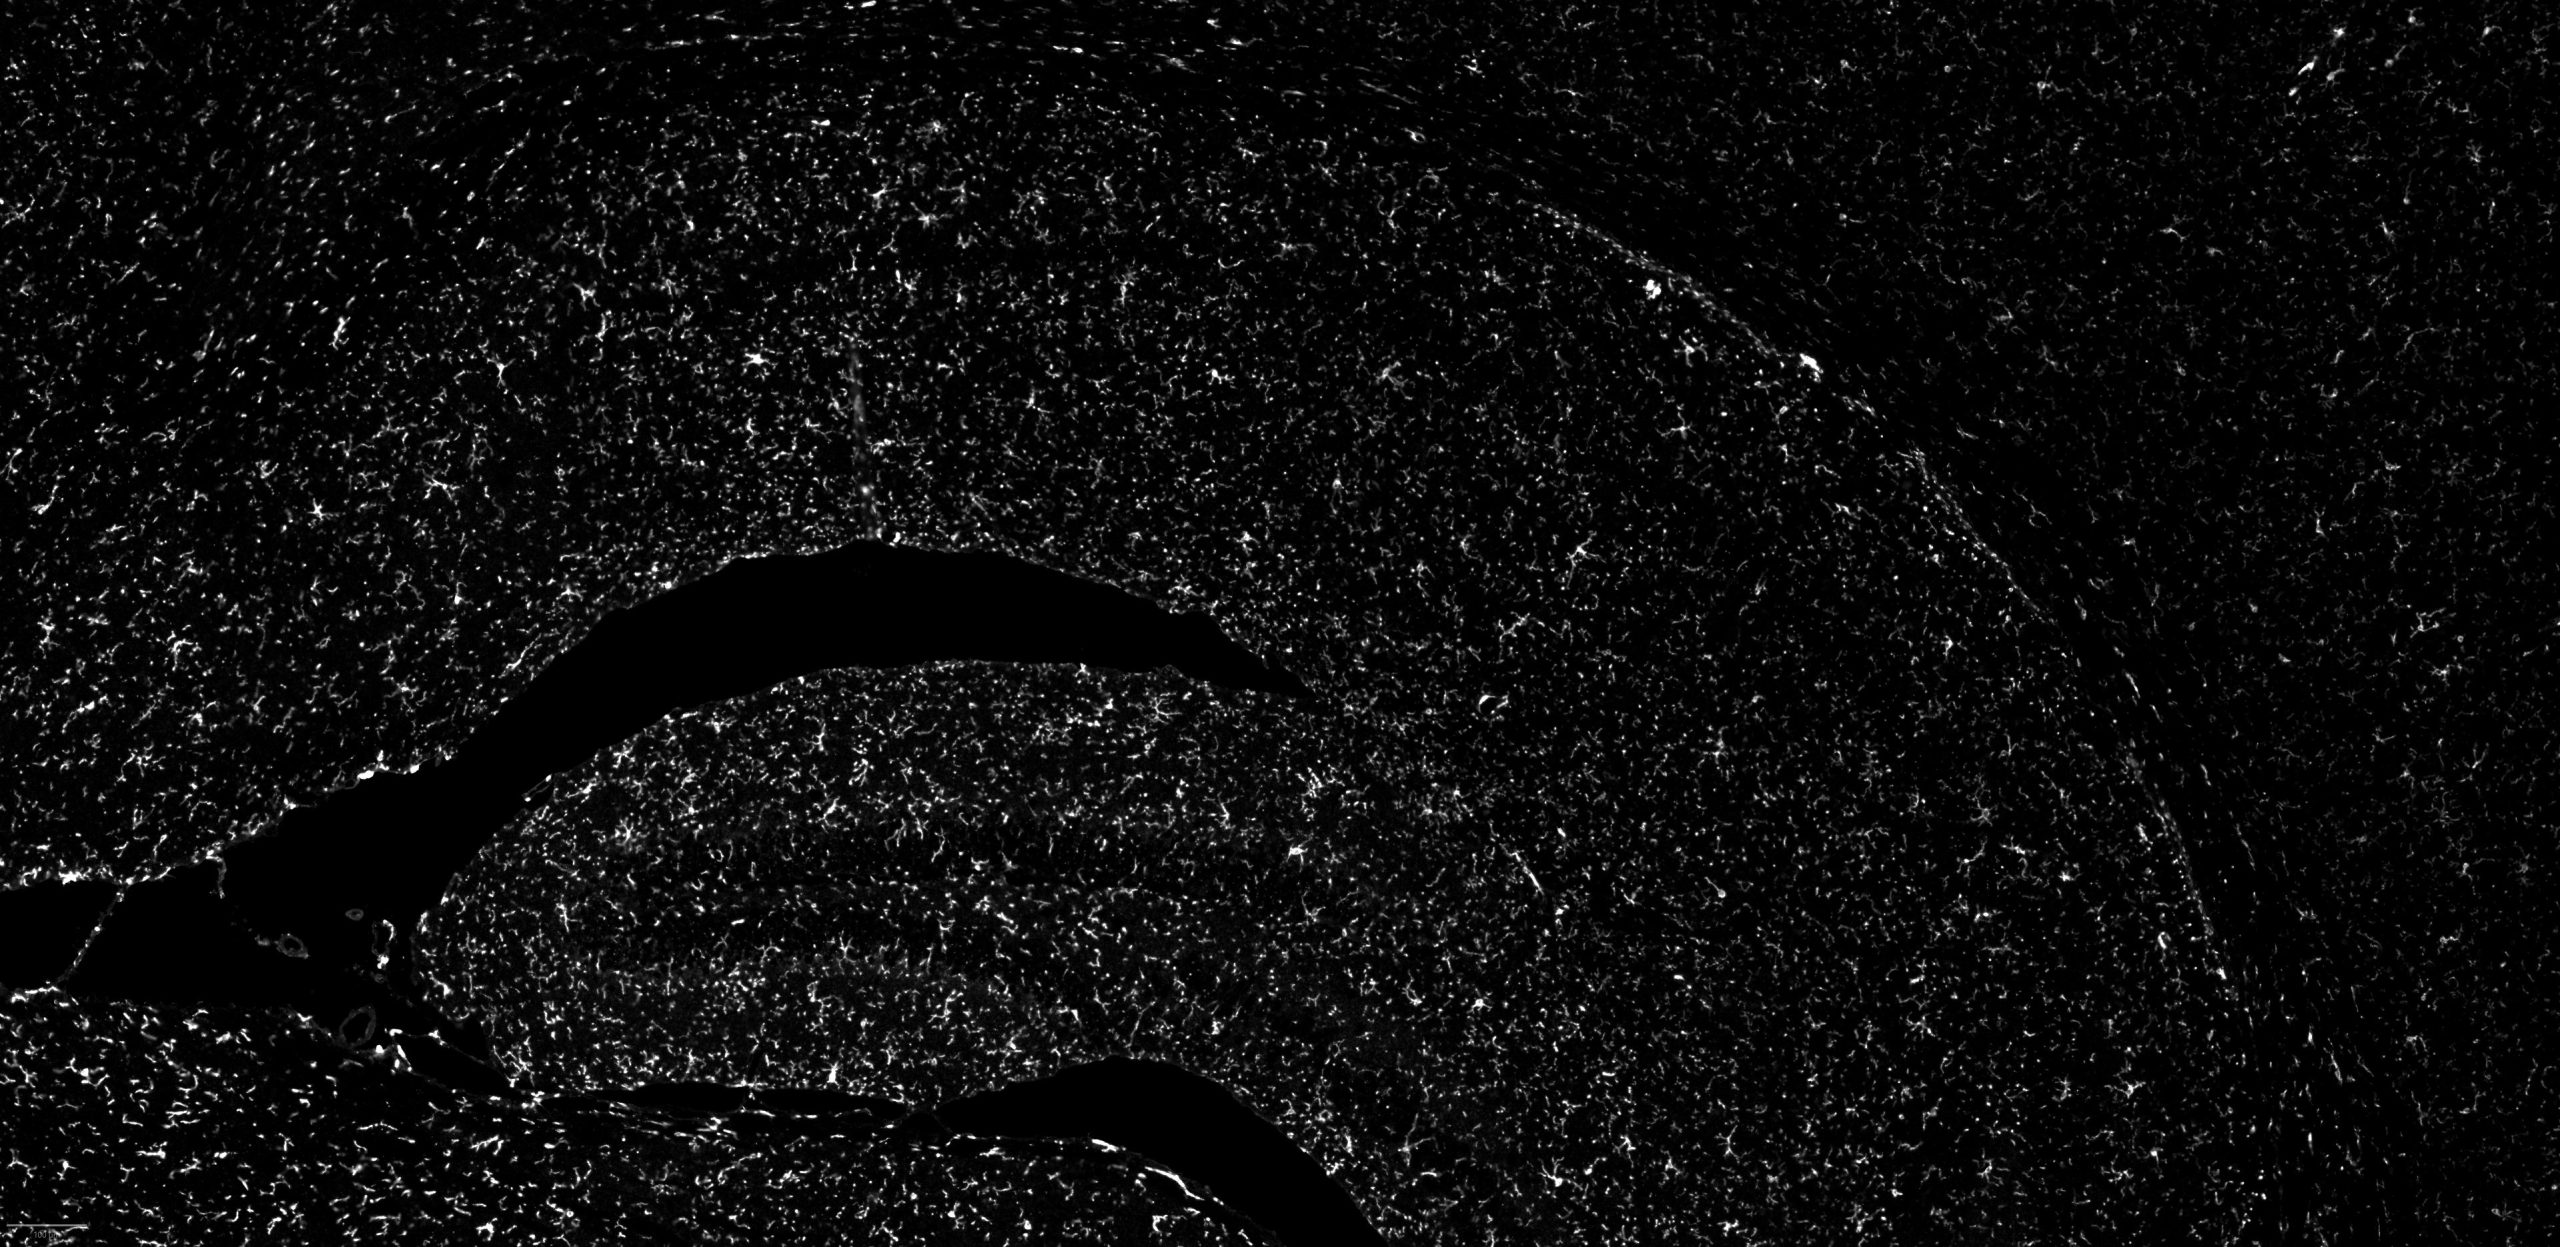

FFPE mouse brain stained with CFP assay

DAPI

NeuN

GFAP

CALB2

Olig2

MBP

CD31

S100b

TMEM119

Iba1

SMMHC